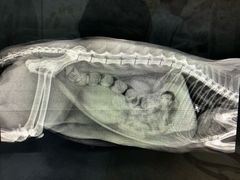

• 思宇宠物医院

• -思宇宠物医院

熊熊流 | 18-07-28

xixi417 | 18-07-13